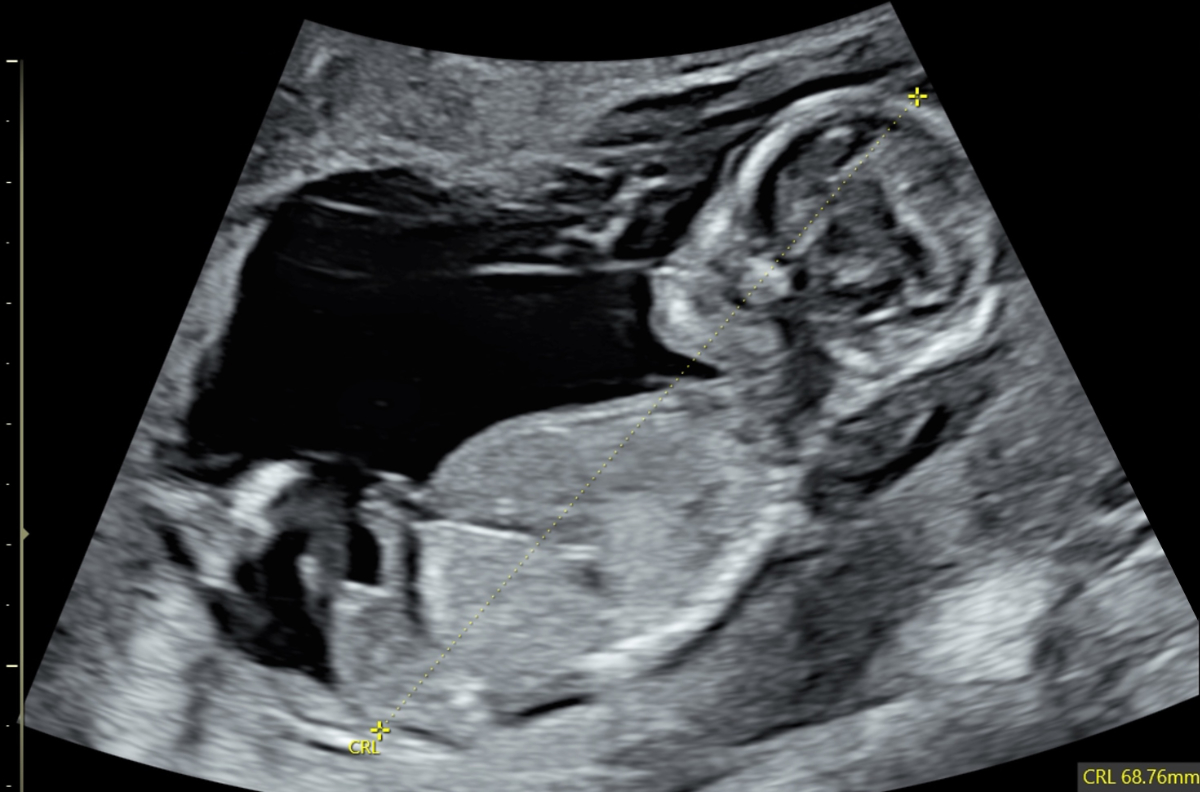

Figure 5Abnormal profile and missing nose in a 13-week foetus (CRL 68.76 mm). CRL: crown-rump length.